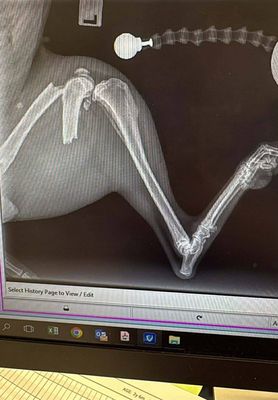

This sweet girl found herself in the care of Southern Rangitikei Vet Services with a broken leg. This week, she will be receiving a fairly large surgery to fix with plates and screws.

We are expecting this to cost from $3,000+, and it will take approximately 6 to 8 weeks to heal.

Yesterday she went under the knife and is now officially part bionic. It was a huge day for her — and for everyone who helped make it happen.

We are now hoping to get Bronte into hydrotherapy, which will help her safely rebuild strength and mobility without putting too much strain on her healing leg. She will also need a follow-up x-ray to make sure everything is healing as it should.